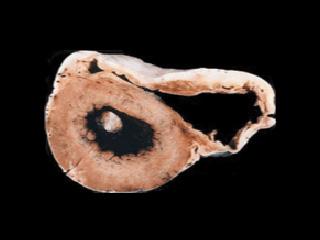

ARVD/C is often patchy in its distribution, so abnormal areas may be surrounded by normal myocardium. If the heart is examined, the right side of the heart may appear to be thickened early in the disease, but later it may become dilated (enlarged) with a thinner wall. The muscle becomes reduced and instead there are thin layers of fat and fibrous tissue. Originally, it was thought that only the right side of the heart was affected, but it is now recognized that the left side of the heart can also be affected.